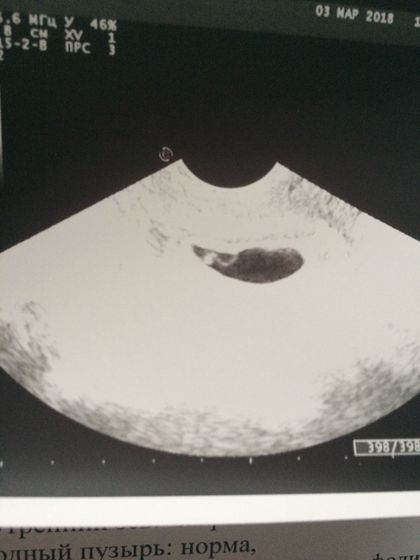

Урааааааа! Нас увидели! Маленькие очень конечно, но есть! Девочки, как же я переживала, сначала, что внематочная, потом, что анэмбриония, теперь наверное до скрининга? ттт, чтоб все хорошо было!❤️ вы только гляньте на эту креветочку?

Акушерский огромный 7 нед и 6 дней, но я точно знаю когда была овуляция и что она была очень поздней, поэтому спокойна))